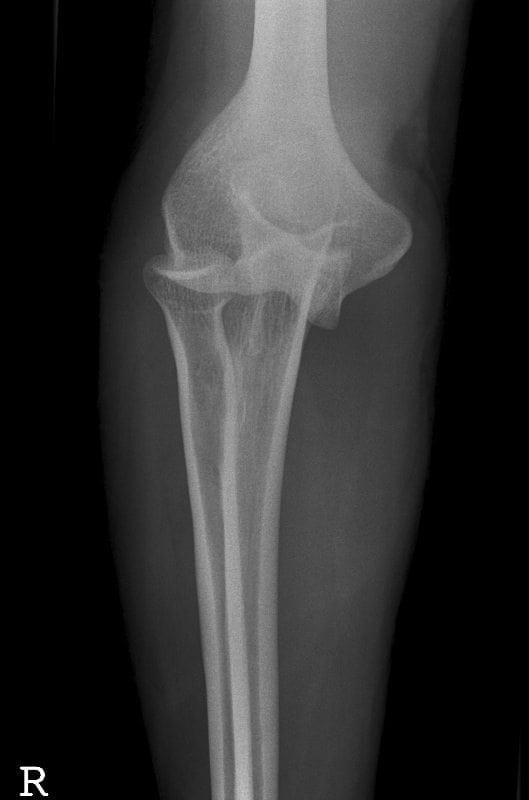

Oh SNAP! Gepost op 28 september 202023 september 2020 door netwerkvsseh Board Review: Oh SNAP! @emdaily.cooperhealth.org Dit delen: Delen op X (Opent in een nieuw venster) X Share op Facebook (Opent in een nieuw venster) Facebook Delen op LinkedIn (Opent in een nieuw venster) LinkedIn E-mail een link naar een vriend (Opent in een nieuw venster) E-mail Afdrukken (Opent in een nieuw venster) Print Vind-ik-leuk Aan het laden... Gerelateerd